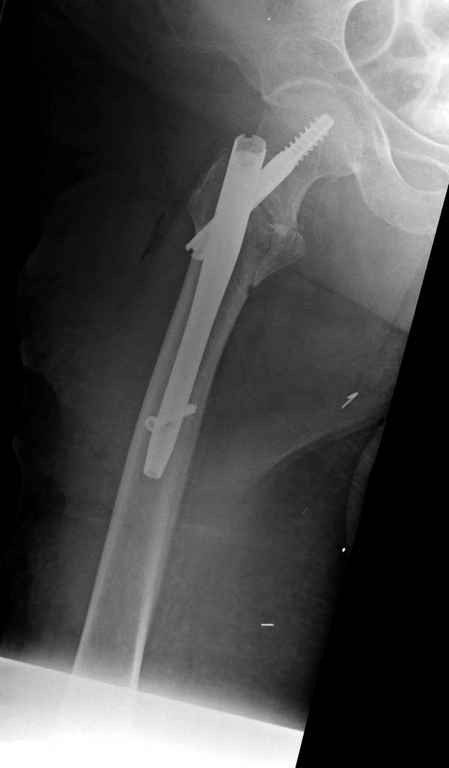

До выхода блокируемых гвоздей для фиксации косых подвертельных переломов в основном применяли Blade Plate. За счет уникальной конструкции создавался Fixed Angled Device, который соединял головку с диафизом, минуя зону перелома.

За счет особой конструкции клинка и подпорки (buttress) в диафиз создавалась стабильность, и предупреждалось скольжение по линии перелома. Перпендикулярная поверхность клинка предупреждала сгибательные и разгибательные смещения, и в сравнении с круглым винтом редко происходило прорезыванием.

Первые реконструкционные гвозди без блокировки винтов не смогли повторить преимущества, и из-за Z эффекта винтов происходило быстрое расшатывание.

С приходом менее агрессивных блокируемых цефаломедуллярных гвоздей (Gamma 3 и другие) изменилась тактика лечения. Несмотря на то, что вся стабильность держится вокруг одного блокирующего винта, в большинстве случаев гвозди приводили к успеху.

Вашему вниманию представляется похожий случай, пациентке 70, осложнился в течение одного месяца после операции. Ревизия с заменой сустава, кабельная фиксация на трохантер. При установке в дистальном диафизе обнаружен тонкий кортикальный слой и сделана профилактика от возможного перелома аллографтом.